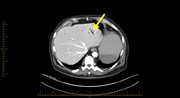

A rare occurrence of hepatic portal venous gas in a patient with chemotherapy-induced enterocolitis: the rise of benign aetiologies

Elizabeth W. Tan and Mark D. Smith

Journal of Surgical Case Reports, Volume 2015, Issue 9, September 2015, rjv114, https://doi.org/10.1093/jscr/rjv114